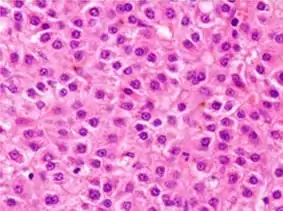

Microscopically, the four architectural and cytological types (patterns) of hepatocellular carcinoma are: fibrolamellar, pseudoglandular (adenoid), pleomorphic (giant cell), and clear cell. In well-differentiated forms, tumor cells resemble hepatocytes, form trabeculae, cords, and nests, and may contain bile pigment in the cytoplasm. In poorly differentiated forms, malignant epithelial cells are discohesive, pleomorphic, anaplastic, and giant. The tumor has a scant stroma and central necrosis because of the poor vascularization.[39] A fifth form – lymphoepithelioma like hepatocellular carcinoma – has also been described.[40][41]

Micrograph of hepatocellular carcinoma. Liver biopsy.

Micrograph of hepatocellular carcinoma. Liver biopsy. Well-differentiated HCC

Well-differentiated HCC Moderately differentiated HCC.